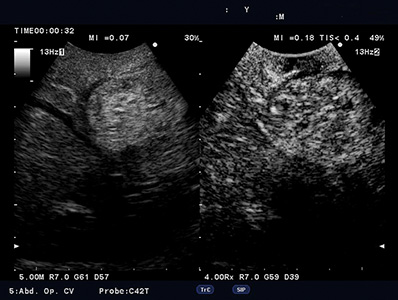

Contrast-specific software is supported for use with contrast agents used with acoustic pressures from low to mid Ml. This is compatible with various transducers.